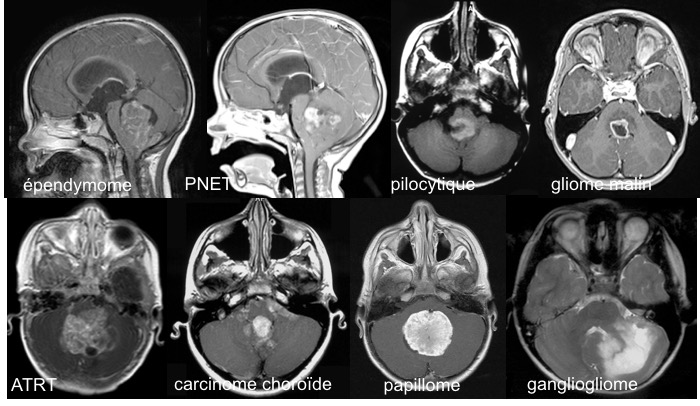

tumeurs fosse post